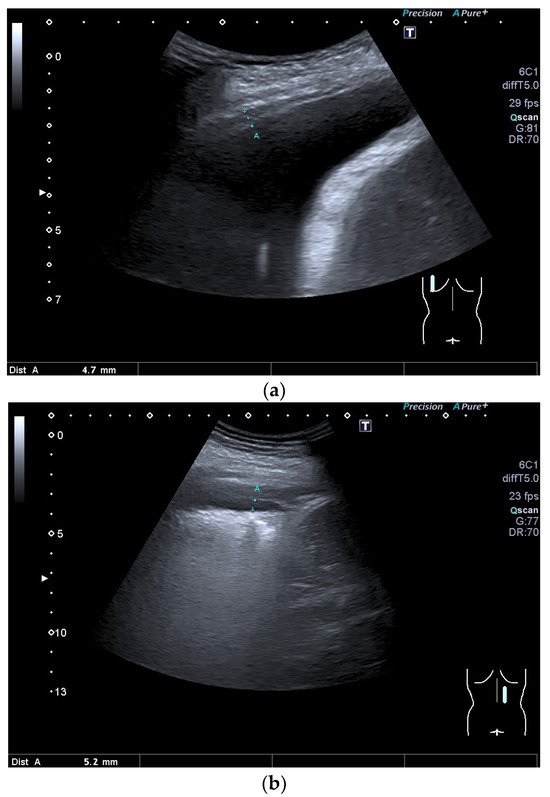

| Fibrothorax | Extensive and dense fibrosis of the visceral pleura, with fusion of the visceral and parietal pleural layers, no lung sliding. |